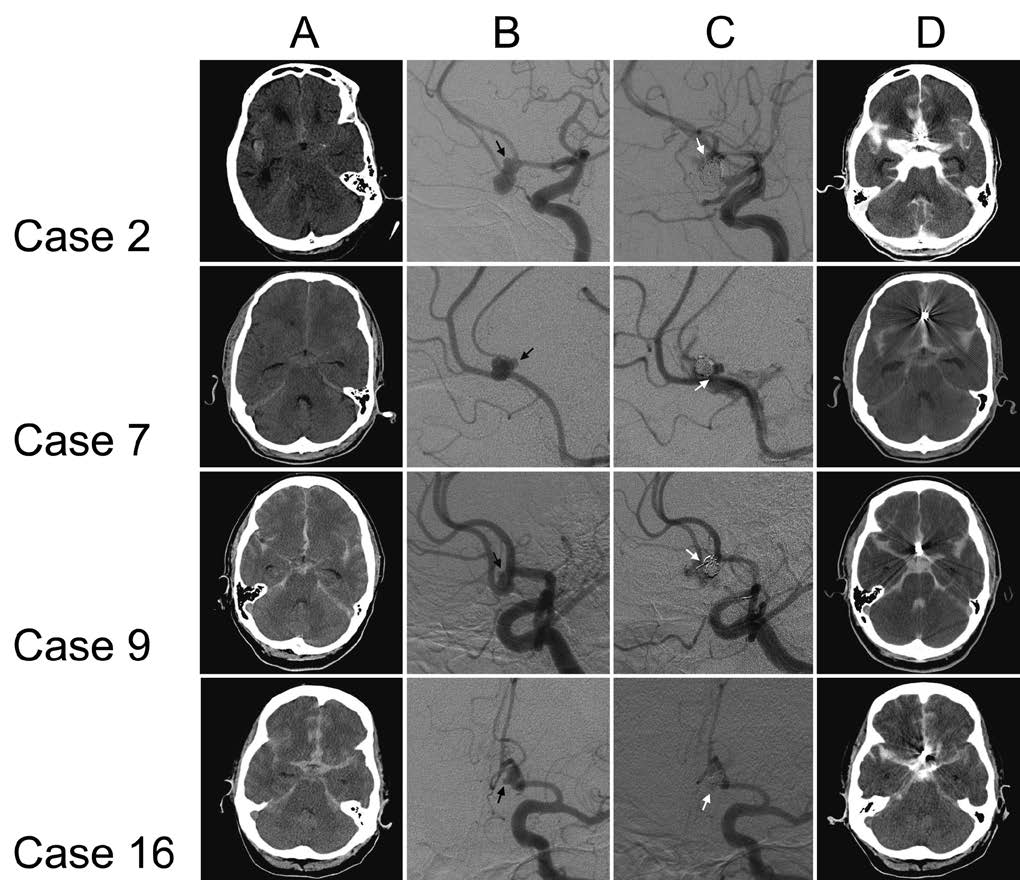

Intraprocedural rupture during coil embolization of ruptured VSIA in a Coil Embolization Ruptured Aneurysm Web rupture of the intracranial aneurysms is associated with a high risk of bleeding and a high incidence of mortality. Web coil embolization is an alternative to clipping for intracranial aneurysms. Web the international subarachnoid aneurysm trial (isat) was the only large, multicenter, randomized clinical trial that compared neurosurgical. Web in ruptured aneurysms, the rates of thromboembolic complications and intraoperative. Coil Embolization Ruptured Aneurysm.